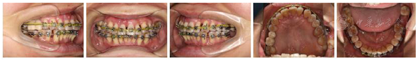

(1)正面观面上1/3比例稍短,面下1/3高度正常;颏部右偏2 mm;上下颌牙齿中线与面中线不一致;上颌中线右偏3 mm;下颌中线右偏2 mm;侧貌突;双侧颞下颌关节区无压痛及弹响,开口度及开口型未见异常;11、21根尖区瘘管;右侧尖牙、磨牙关系远中关系,左侧尖牙、磨牙远中关系;覆盖Ⅲ°,覆合Ⅰ°;上前牙牙轴均向右侧倾斜,15、16联冠,上颌间隙6 mm,37牙列缺失,下颌拥挤度3.5 mm(图1,图2)。(2)牙周会诊检查:口腔卫生欠佳,菌斑指数PLI:2~3,牙石(++~+++),色素(+~++)。全口牙龈色暗红,牙龈厚钝,质地松软,牙龈无剥削。探诊深度PD>3 mm,附着丧失AL+,牙龈出血指数BI:2~4,BOP(+)。根分叉病变FI:Ⅱ,11、22松动Ⅲ°,23松动Ⅱ°,12、36~41松动Ⅰ°(图3)。